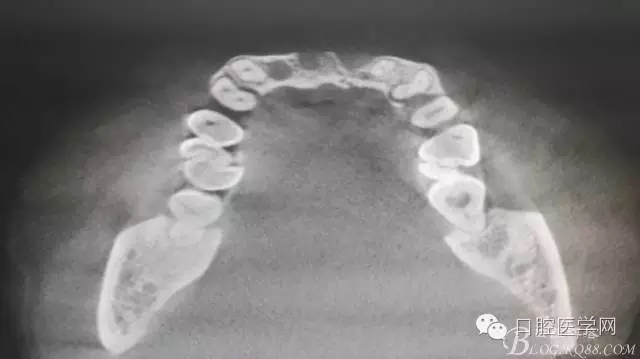

為他院轉(zhuǎn)診患者。男,無吸煙史,前牙因齲壞治療后,外力折斷導(dǎo)致拔除?,F(xiàn)拔除該牙后兩個多月。 左上區(qū)域骨寬度不足,計劃植入種植體同期GBR。

左上區(qū)域骨寬度不足,計劃植入種植體同期GBR。